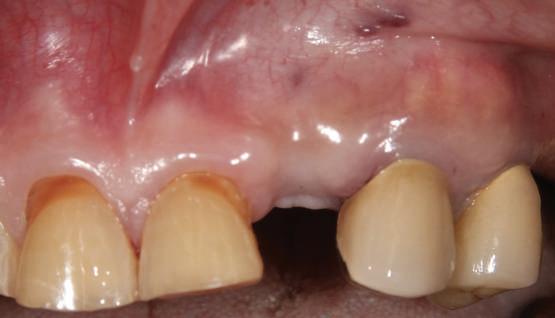

Acest pacient s-a prezentat cu o punte 1.3.-2.3. compromisă.

Pentru a păstra limitele restaurării fixe pe toată durata tratamentului, s-au inserat în primă etapă implanturi corespunzător 1.3. şi 2.3. După integrarea acestora, s-au aplicat bonturi individualizate, iar restaurarea provizorie s-a rebazat pentru suplimentarea suportului.

Implanturile şi bonturile ulterioare aferente s-au putut poziţiona în poziţiile 1.2. şi 2.1. Incisivul 1.1. a beneficiat de tratament endodontic electiv pentru a fi redus şi în cele din urmă, după inserarea bonturilor pe implanturile 1.2. şi 2.1., a fost scufundat (fig. 20, 21).

Atitudine: În fig. 21, este evident că, după submersiunea radiculară, nu se

obiectivează recesie în jurul bonturilor 1.2. şi 2.1. De notat osul excelent vestibular în dreptul tuturor implanturilor, fără recesie în jurul 1.3. şi 2.3. (fig. 22) care au fost inserate cu 8 luni înainte de 1.2. şi 2.1. Perioada scursă între scufundarea rădăcinii (fig. 20) şi inserarea punţii finale (fig. 22) a fost de 7 luni (fig. 23).